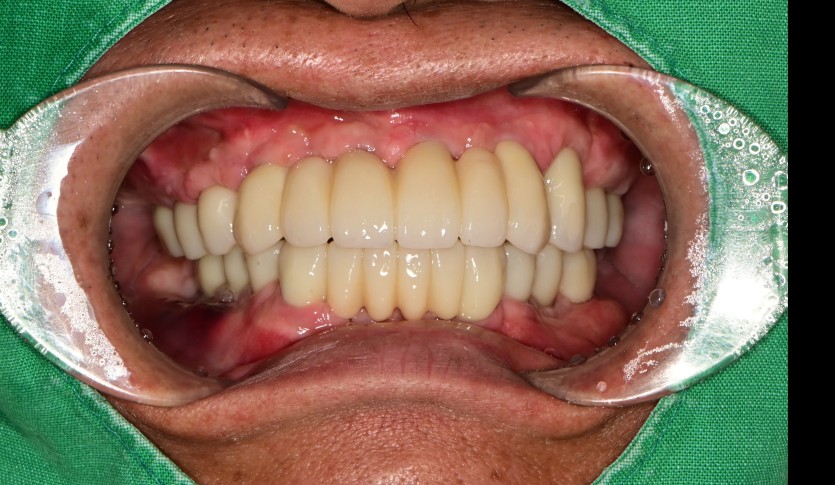

만 52세 전악 상악, 하악 전체 임플란트 증례

전악 전체 임플란트 증례입니다.

18개의 임플란트로 완성하였습니다.